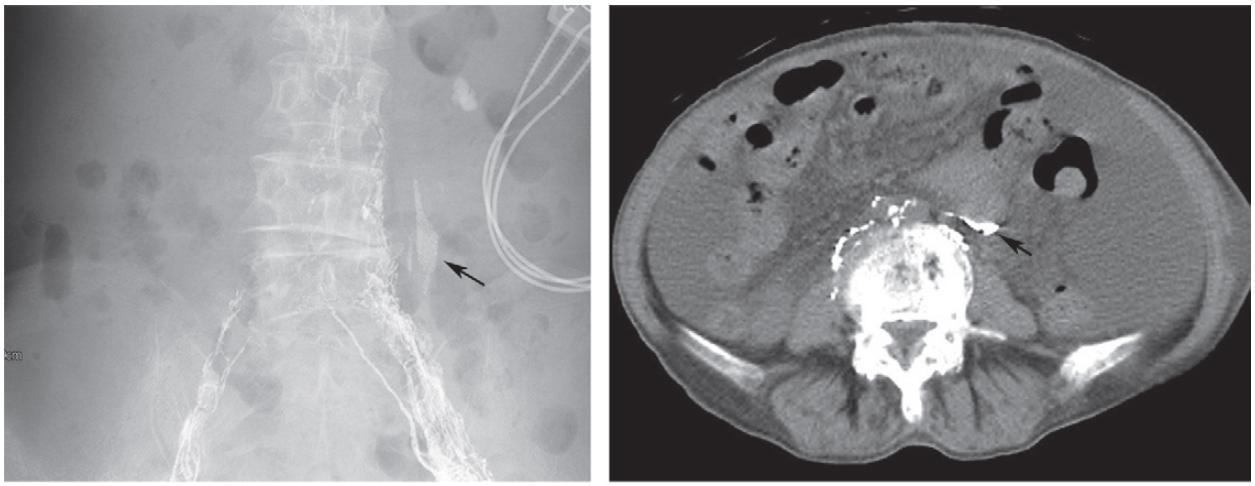

复发/难治性盆腔淋巴囊肿可尝试应用淋巴管栓塞术。在超声引导下,应用微穿针穿刺,微穿针远端置于淋巴结皮质与髓质之间,经微穿针缓慢注入超液化碘油,DSA密切监测淋巴管显影情况,必要时术中CBCT监测淋巴管显影。

超声引导下穿刺淋巴结

当实时显影出现与淋巴囊肿相连接的淋巴管时即可进行栓塞治疗。淋巴管栓塞治疗术后仍需密切观察淋巴囊肿引流量。

淋巴管造影+栓塞治疗